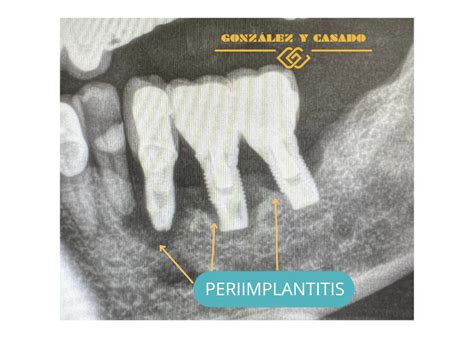

Para que puedas entender lo que puede ocurrir, la periimplantitis dental es una enfermedad inflamatoria que afecta al tejido que rodea un implante dental, lo que puede hacer que perdamos progresivamente el hueso de soporte a causa de la infección. La periimplantitis es conocida, coloquialmente, con el nombre de “periodontitis de los implantes”. Esto se debe a que las causas que originan ambas enfermedades son, por lo general, las mismas: la falta de higiene bucodental.

- Periimplantitis: En la periimplantitis hay una pérdida grave del hueso que hace peligrar la fijación del implante.

Entre las causas de la periimplantitis la más común es la acumulación de placa bacteriana y sarro alrededor del implante debido a una falta de higiene o de revisiones en el dentista. Esta acumulación de placa bacteriana provoca una infección que afecta a los tejidos que rodean el implante. En segundo lugar, los daños alcanzan al hueso, que actúa de soporte del implante. La acumulación prolongada de placa bacteriana propicia la aparición de bacterias periodontopatógenas que alteran el equilibrio del microbioma oral (disbiosis).